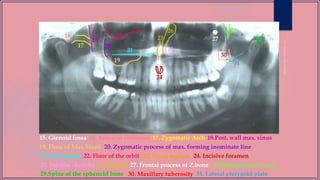

15. Glenoid fossa

19. Floor of Max.Sinus

17. Zygomatic Arch16. Articular eminence 18.Post. wall max. sinus

20. Zygomatic process of max. forming inominate line

21. Hard palate 22. Floor of the orbit 23. Nasal septum 24. Incisive foramen

25. Inferior choncha 26. Meatus 27. Frontal process of Z.bone

28.Pterygo max. fissure

30. Maxillary tuberosity29.Spine of the sphenoid bone 31. Lateral pterygoid plate

32. External acoustic meatus 34. Shadow of ear lobe33. Styloid process

35. nose 36. Shadow of Cervical spine

37. Nasopharyngeal space 38. Shadow of uvula

39

39. Submandibular fossa